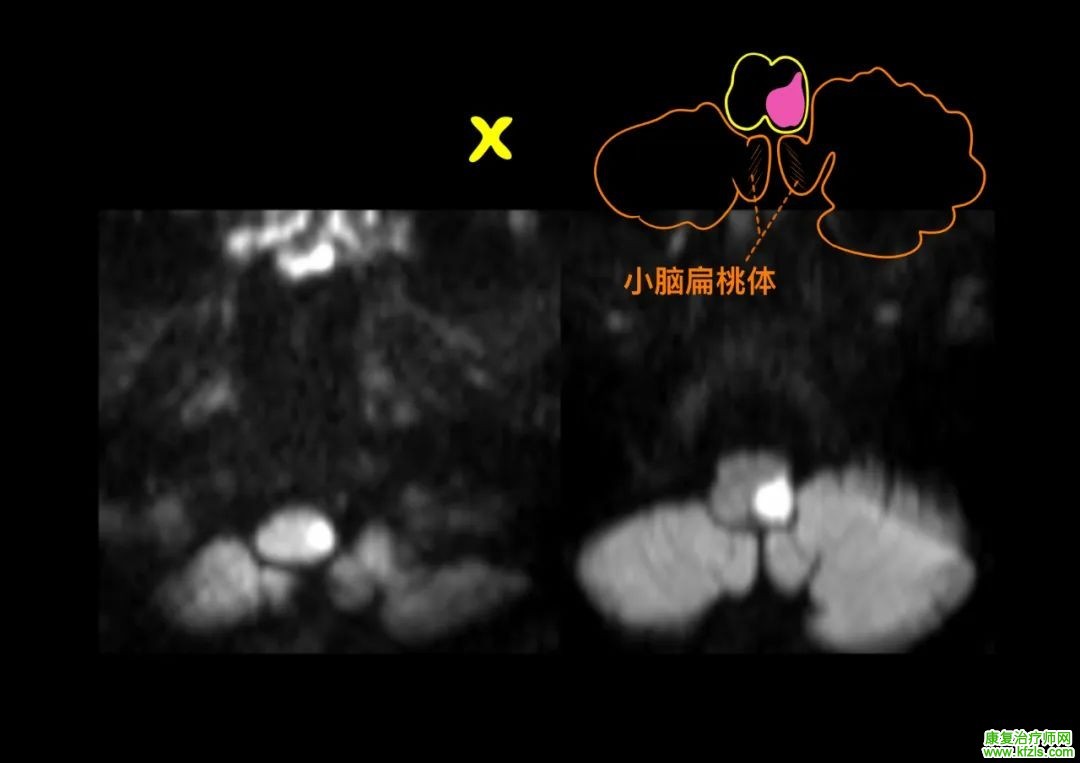

52 岁男性,既往「高血压」病史,以「头晕伴言语不清、口角歪斜 15 d」为主诉入院,患者 15 d 前无明显诱出现头晕,伴恶心、呕吐、全身出汗,未诊治;后症状逐渐加重出现视物重影、言语不清、饮水呛咳,查体:构音障碍,双眼球左右运动不能,上下运动正常,无眼震。右侧额纹消失,右眼闭目无力,右侧鼻唇沟浅,示齿口角左偏,右侧鼓腮漏气,Romberg 征(+),走「一」字不稳。头颅核磁提示双侧脑桥被盖部梗死:

脑干梗死

病例来源:参考文献